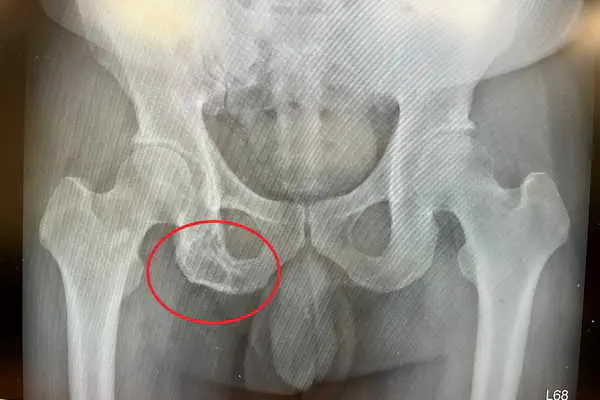

白先生以為工作勞累才導致臀部疼痛,只去做復健和民俗整復,痛到無法忍受才到醫院就醫。白先生電腦斷層檢查影像發現坐骨骨頭被侵蝕的病灶,轉診到台中慈濟醫院血液腫瘤科。黃冠博醫師抽血檢驗多項腫瘤指數都是正常,進一步做血液蛋白質免疫電泳分析,發現血清中的單株球蛋白濃度異常升高,再經由骨髓切片檢查,確診為「多發性骨髓瘤」造成的骨骼病變與「單株丙型免疫球蛋白血症」。

圖二:白先生的坐骨骨頭已被侵蝕。